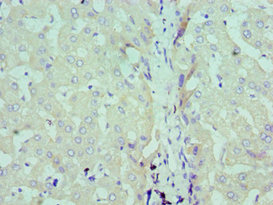

Immunohistochemistry of paraffin-embedded human liver tissue using CSB-PA020888ESR2HU at dilution of 1:100